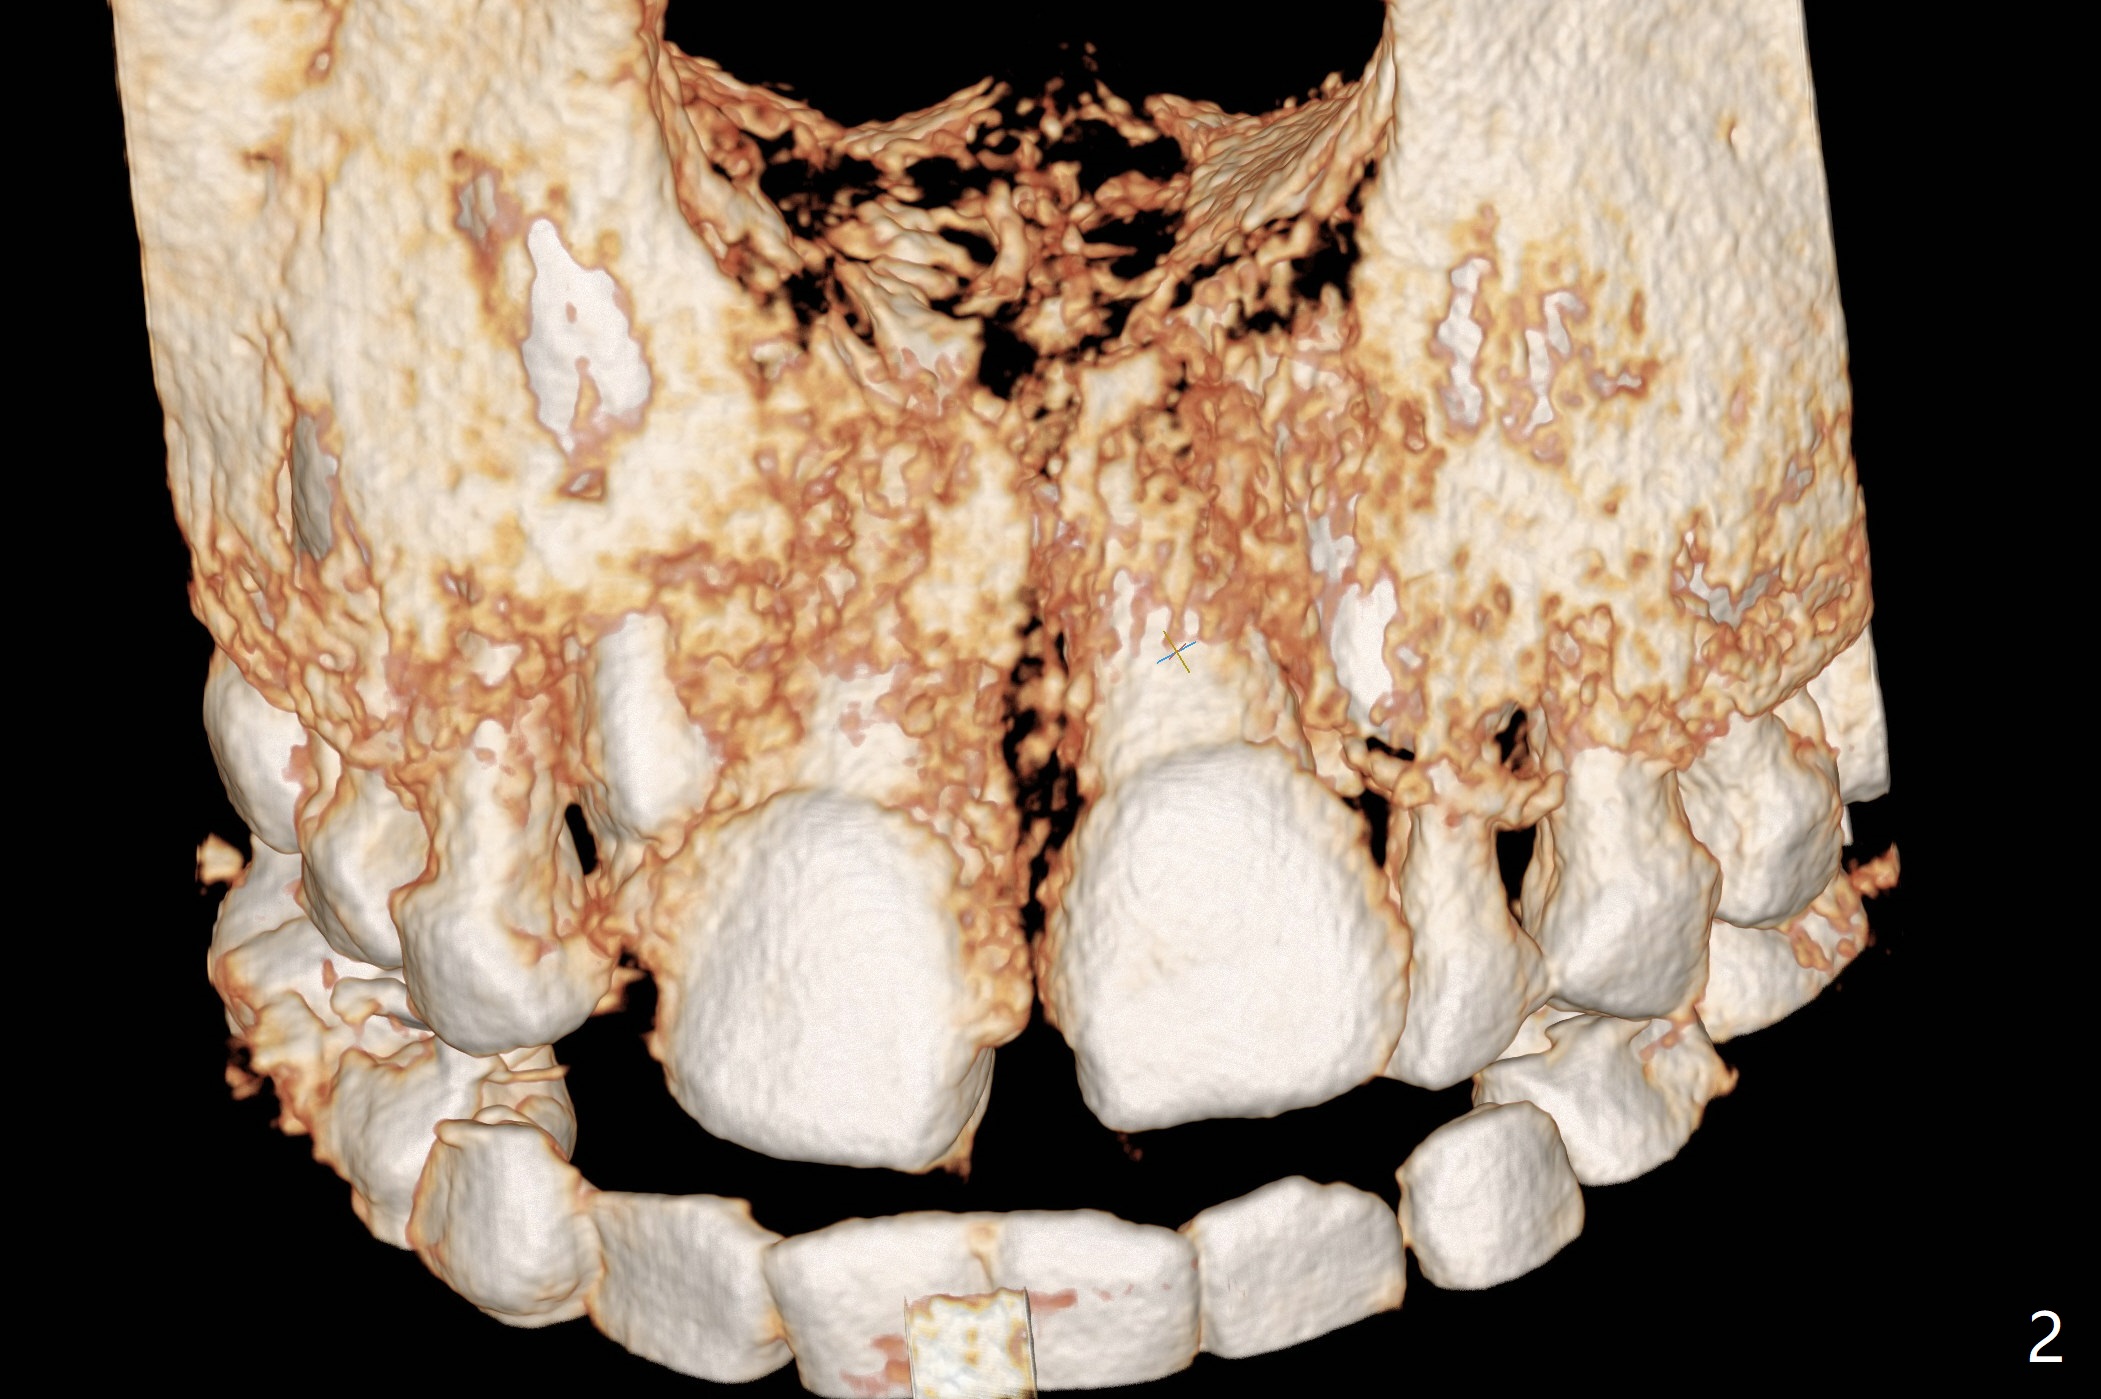

The father of a 7-year-old boy wonders why the upper central incisors, particularly #9, are off (Fig.1 3-D CT tooth coloring). Fig.2 (bone coloring) does not reveal much. Fig.3 (MIP, more transparent) reveals a supernumerary tooth, called mesiodens (M, an extra central incisor, abnormally shaped (cone), near the midline). Palatal view shows that the mesiodens points to the midline and distal (arrow). A palatal gingival sulcus incision will be made to expose the extra tooth (Fig.5). An elevator will be used as midline and distal as possible to avoid damage to the root of #9 and the tooth bud of #10 (Fig.6 MIP). Photos will be taken frontally and palatally preop and after incision and exposure of the mesiodens (palatal).